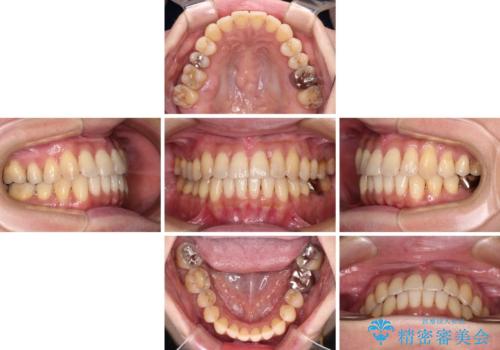

- 前歯のクロスバイトが気になり、インビザラインによる矯正治療を希望して来院された患者様です。

上顎側切歯(上の真ん中から2番目の歯)が舌側転位している場合、インビザラインでは仕上げきれないことが多く、更には無理して動かそうとすると歯髄壊死を起こすリスクが高いと言われています。

インビザラインで歯列を移動する前に、上顎前歯をワイヤー矯正で整え、その後上下歯列をインビザラインにて矯正治療を行うこととしました。